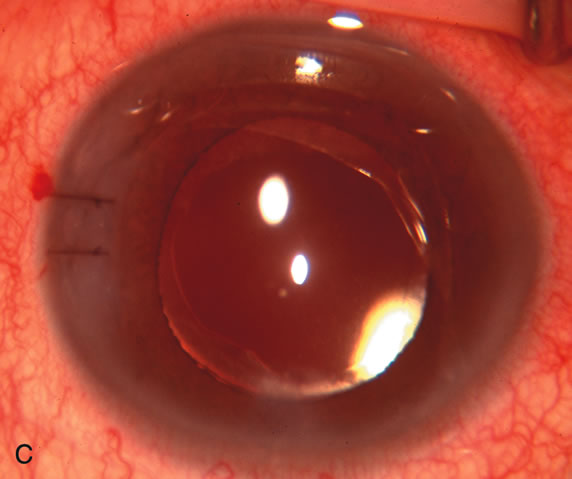

Fig. 1. The anatomic advantage of small incision cataract surgery for the glaucoma patient. A. Long-term bleb function with a large cataract incision is difficult to achieve with either ECCE-trabeculectomy or trabeculectomy followed later by ECCE. This bleb failed to form sufficiently when combined with large incision ECCE. The inflammation, bleeding, and long-term wound healing with stimulation of fibroblasts associated with this technique are more likely to cause bleb failure. In addition, the increased iris manipulation necessary to deliver the nucleus and subsequent iris repair adds to the long-term breakdown of the blood aqueous barrier. B and C. Two-site phacotrabeculectomy has the advantage of small incision cataract surgery combined with separate site trabeculectomy. The incision size is one third the size of the standard ECCE. The inflammation is less severe, and cataract wound healing is confined to the temporal area. Visual rehabilitation with phacoemulsification and foldable IOL is much faster. Phacoemulsification allows successful lens extraction even in the unfriendly environment of a smaller pupil compared with ECCE. The trabeculectomy is performed in an entirely different site, well away from the wound healing associated with temporal phacoemulsification. The likelihood of this filter functioning long-term is greater than with ECCE-trabeculectomy. D. The surgeon also has the option of single-site phacotrabeculectomy with foldable IOL. Both the lens extraction and trabeculectomy are performed through one small 3.5-mm limbal incision.

Fig. 3. Partial bleb failure following clear corneal phacoemulsification with foldable IOL. A. Preoperative bleb appearance prior to temporal lens extraction. Preoperative IOP was 12 mm Hg on no antiglaucoma medications. Time from 5-FU trabeculectomy surgery to lens extraction was one year. B. Bleb appearance 2 months after clear corneal cataract surgery with topical anesthesia. Following lens extraction, increased vascularity was noted along with decreased size of the filtering bleb. IOP increased to 20 mm Hg as early as 2 weeks after surgery, necessitating topical antiglaucoma therapy. C. High magnification view of bleb before lens extraction demonstrates diffuse pale bleb. D. High magnification view of bleb 2 months after surgery. There are vessels surrounding the nasal side of the bleb and the overall bleb size is smaller.